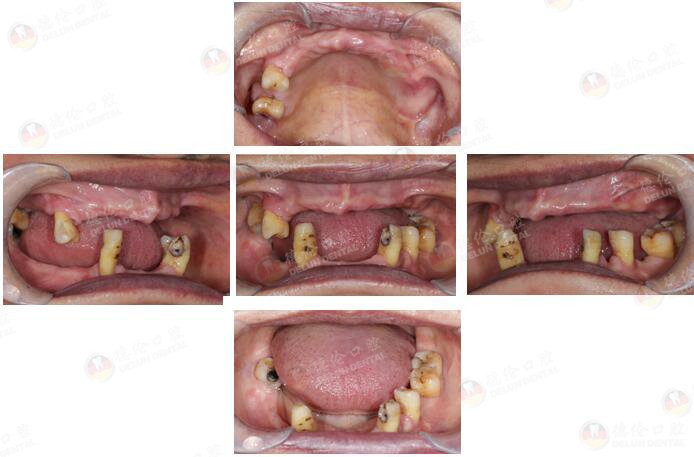

许女士 65岁

牙齿症状:全口多牙缺失十余年。

10余年前因牙周炎致全口多牙拔除,之后利用活动假牙修复,现在出现活动假牙固位差、牙龈游走性压痛等情况,希望做种植牙修复。

治疗方式:倾斜植体避开左侧上颌窦、整体支架修复、数字化3D导板种植